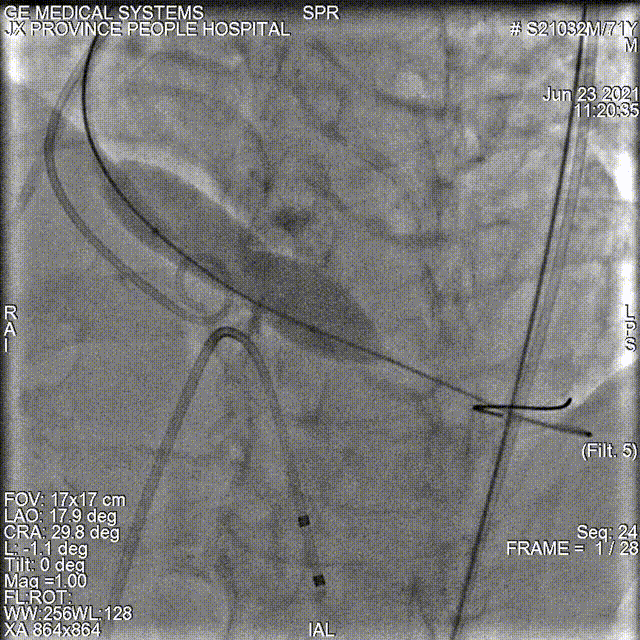

20mm球囊进行后扩

最终造影显示瓣膜仅微量反流

术后即刻超声良好:平均压差:8.0mmHg ;微量瓣周返流。